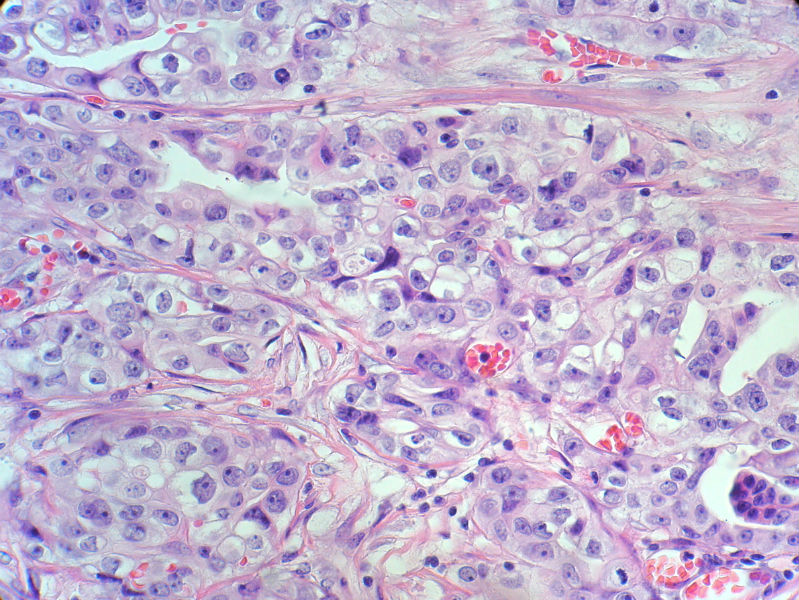

肿瘤呈巢片状分布,细胞大小相对一致,胞浆丰富,胞核呈细颗粒状,可见小核仁,血管较丰富,考虑神经内分泌肿瘤,加做免疫组化(Ki67、Syn、NSE、CgA、CD56)分级。

神经内分泌肿瘤,加做免疫组化(CKp、Ki67、Syn、NSE、CgA、CD56)分级。